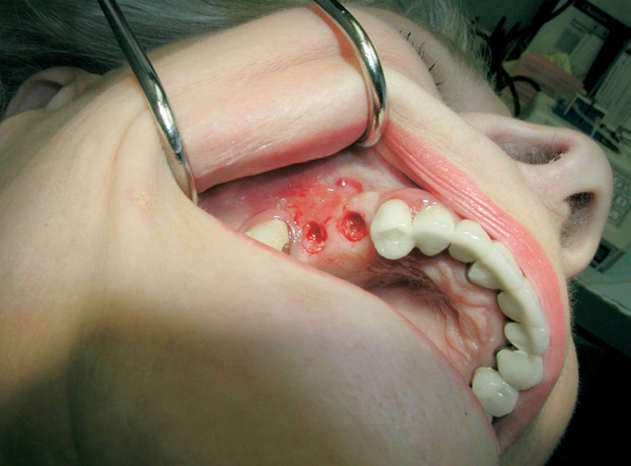

Nejlepším materiálem pro augmentace je vlastní kost pacient, kterou můžeme získat

např. odběrem z dolní čelisti pacienta. Jedná se o velmi šetrný, nenáročný výkon, který pacienta nijak nezatíží.